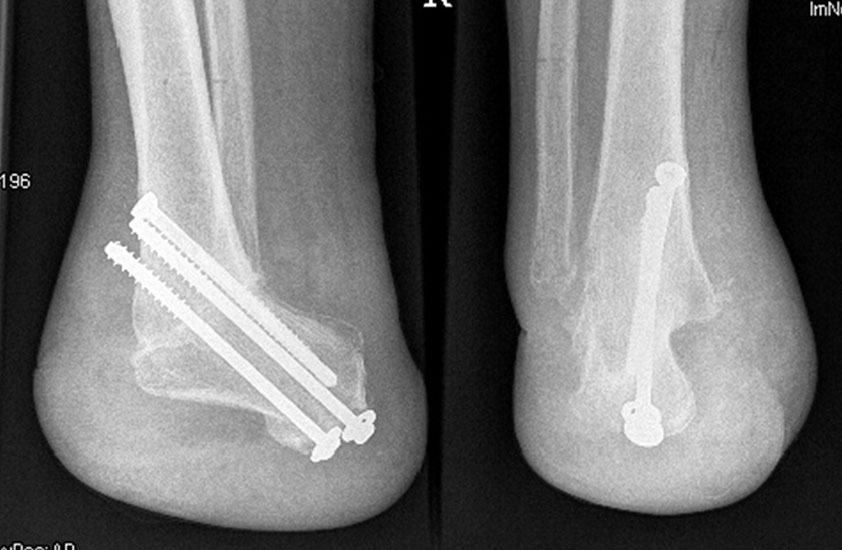

Zur Osteosynthese bevorzugen wir 2-3 kanülierte Großfragmentschrauben (Abb. 49). Postoperativ ist die Extremität für 8 Wochen zu entlasten, wobei zur Sicherheit eine Entlas­tungsorthese verordnet werden kann. Bei schwachen oder unzuverlässigen Patienten empfiehlt es sich, für 8 Wochen einen Ring-Fixateur anzulegen.